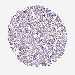

LIVER CANCER - Protein expressioni

A mouse-over function shows sample information and annotation data. Click on an image to view it in a full screen mode. Samples can be filtered based on level of antibody staining by selecting one or several of the following categories: high, medium, low and not detected. The assay and annotation is described here.

Antibody stainingi

Antibody staining in the annotated cell types in the current human tissue is reported as not detected, low, medium, or high, based on conventional immunohistochemistry profiling in selected tissues. This score is based on the combination of the staining intensity and fraction of stained cells.

Each image is clickable and will lead to virtual microscopy that enables deeper exploration of all samples and also displays staining intensity scores, fraction scores and subcellular localization as well as patient and tissue information for each sample.

Antibody HPA049031

Staining

High

Medium

Low

Not detected

Intensity

Strong

Moderate

Weak

Negative

Quantity

>75%

75%-25%

<25%

None

Location

Nuclear

Cytoplasmic/membranous

Cytoplasmic/membranous,nuclear

Cholangiocarcinoma

Carcinoma, Hepatocellular, NOS